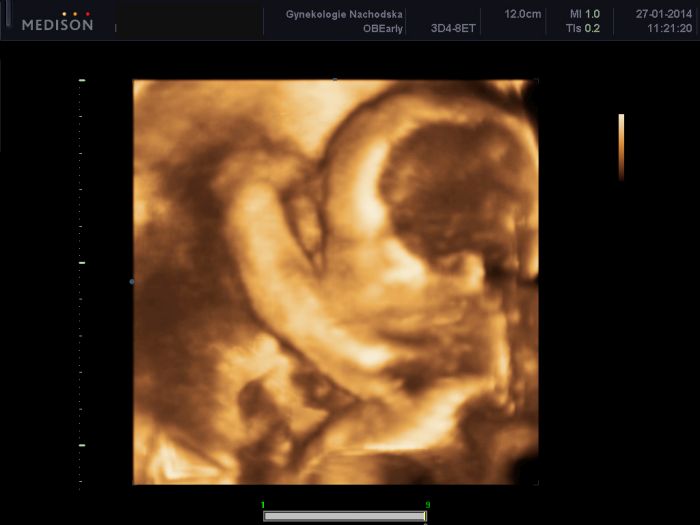

Ahoj holky, tak kontrola u mé Dr. proběhla dle očekávání a vše je v pořádku, zítra ještě velký UZ :-) Stále neobjevila pindíka, takže to pořád spíše vypadá na Emu :-) A samozřejmě se s ní pochlubím v celé své kráse :-) Váhový odhad je asi 530g.